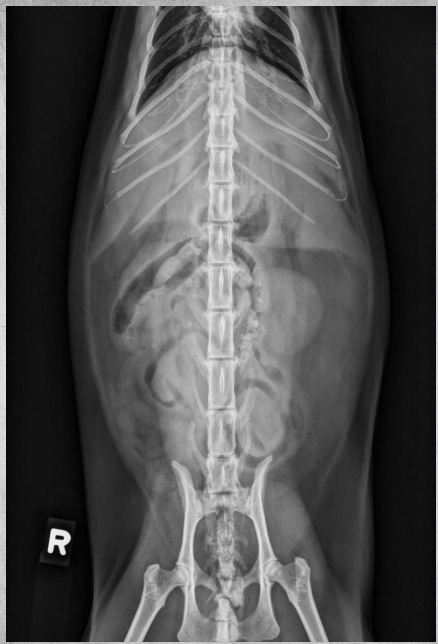

●6 mo female Great Dane

●Vomiting, loss of appetite for 3 days

●Suspected foreign body

● Entire small intestine moderately homogenously fluid filled, teeny bubbles throughout GI tract indicating GI hypomotility.

● Markedly gas-distended intestinal segment in mid-abdomen, reverse C-shaped, most likely normal caecum.

● Diffusedly fluid filled GIT with interspersed gas bubbles is most consistent with functional ileus from severe enteritis.

● No radiographically evident foreign body.

● Dx: Parvoviral enteritis